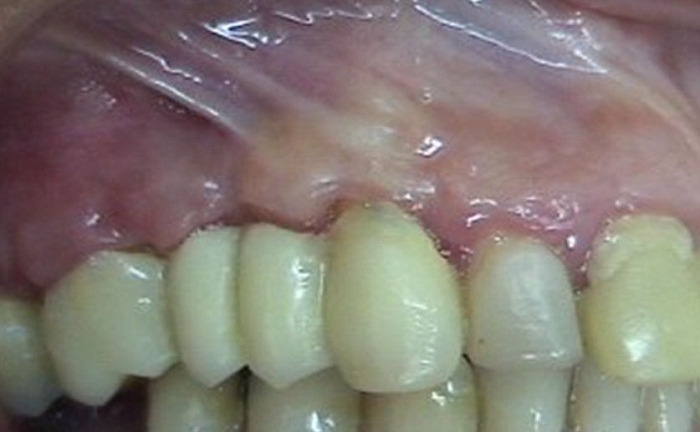

Se le drenó el absceso a la paciente por medio de una incisión a la altura coronal. En el mismo acto se tomó un cultivo en medio de transporte VMGAIII. Se encontraron los microorganismos Porphyromonas gingivalis (1,66 %), Prevotela intermedia/nigrescens (8,88 %), Tannerella forsythia (0,5 %), Campilobacter spp. (0,5 %), Eubacterium spp. (0,5 %), Fusobacterium spp. (6,66 %), Parvimonas micra (0,05 %) y Eikenella corrodens (6,11 %). A partir de estos hallazgos y la prueba de sensibilidad antibiótica, se prescribió amoxicilina de 500 mg, 1 tableta cada 8 h durante 5 días, más metronidazol de 500 mg, 1 tableta cada 8 h durante 5 días. La paciente regresó a control entre una y 4 semanas después, tiempo al cabo del cual se observó la resolución completa del absceso (figura 4).

En este caso presentado, los signos y los síntomas de la complicación fueron leves. Su tratamiento fue conservador y consistió en curetaje de la zona y administración de antibióticos. Se ha realizado seguimiento clínico de la paciente sin observarse recurrencia del absceso o desarrollo de un quiste detectable. La evolución clínica del procedimiento fue favorable y, al parecer, no se afectó negativamente por el desarrollo del absceso.